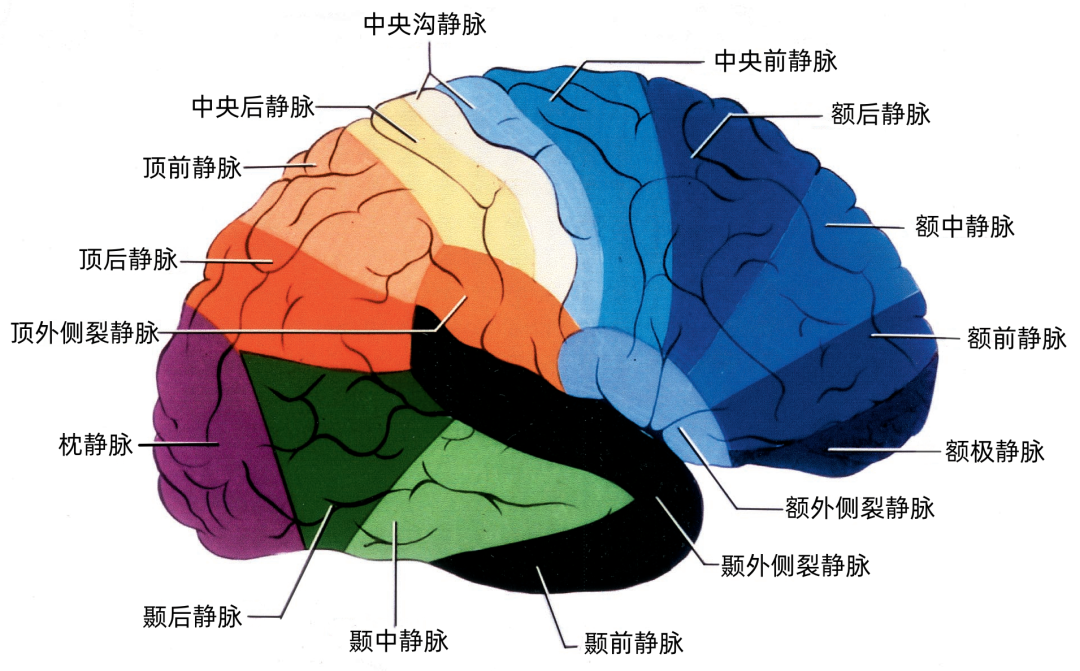

根据引流半球外侧面、内侧面或底面,皮层静脉分为三组。三个面的皮层静脉可依据其引流的脑叶和皮层区进一步细分。皮层静脉引流区域和方向如下: 额叶外侧面(蓝色)由额极静脉、额前静脉、额中静脉,额后静脉、中央前静脉、中央静脉、额外侧裂静脉引流。 顶叶外侧面(黄色)由中央静脉、中央后静脉、顶前静脉、顶后静脉、顶外侧裂静脉引流。 颞叶外侧面(绿色)由颞前静脉、颞中静脉、颞后静脉、颞外侧裂静脉引流。

大脑外侧面的静脉引流方向

额叶外侧面的静脉按引流方向由两种蓝色标出:浅蓝色为上升的静脉。进入上矢状窦。深蓝色为下降的静脉,进入外侧裂浅静脉。

升支静脉包括额极静脉,额前静脉,额中静脉、额后静脉、中央前静脉、中央静脉。降支包括额外侧裂静脉。

顶叶外侧面的静脉按引流方向由两种红色标出:浅红色为上升静脉,进入上矢状窦。深红色为下降静脉,进入外侧裂浅静脉。

升支静脉包括中央静脉、中央后静脉、顶前静脉、顶后静脉,Trolard静脉相当于大的中央后静脉。降支包括顶外侧裂静脉。

枕叶外侧面的引流静脉由紫色标出:它们主要是一些上升静脉,称为枕静脉,进入上矢状窦。一些小的枕静脉可能向下进入横窦和小脑幕窦。

颞叶外侧面的静脉按引流方向由两种绿色标出:浅绿色为上升静脉,进入外侧裂浅静脉。深绿色为下降支,进入小脑幕窦。

升支静脉是颞外侧裂静脉。降支包括颞前静脉、颞中静脉、颞后静脉

▼1.额叶

额叶的引流静脉分为外侧面组、内侧面组、底面组。外侧面组分为上升组,汇入上矢状窦;下降组,引流向外侧裂,进入外侧裂浅静脉。 上升组静脉包括额极、额前、额中、额后静脉,中央前静脉和中央沟静脉。这些静脉可能在回流至上矢状窦前与相邻的底面组、内侧面组的静脉汇合; 下降组由额外侧裂静脉组成。上升组引流的区域大于下降组。 额叶外侧面静脉及其引流区域如下:额极静脉引流额下回、额中回和额上回前部;额前、额中、额后静脉引流额极和中央前回之间的额叶前、中、后部凸面;中央前静脉引流中央前回下部、额下回盖部和邻近的额下、额中和额上回;中央Rolandic静脉引流中央沟附近的中央前回和中央后回;额外侧裂静脉引流额下回和邻近的额中回下部及中央前回下部。 额叶内侧面由弯曲的扣带沟分为内侧区和外侧区。额内侧静脉分为上升组进入上矢状窦;下降组进入下矢状窦或汇入行经胼胝体的静脉,最后进入基底静脉前端。上升组静脉由前内侧额静脉、中内侧额静脉、后内侧额静脉和旁中央沟静脉组成,它们是额上回内侧和邻近扣带回的主要静脉回流,一般向上弯曲走行,在半球上缘向外加入来自半球外侧组的静脉,然后注入上矢状窦。下降组静脉包括胼周前静脉、终板旁静脉和大脑前静脉。 额叶内侧面静脉及其引流区域如下:额前内侧静脉引流额极后方的扣带回和额上回;额中间内侧静脉引流胼胝体膝部前方的额上回和邻近扣带回的内侧面;额后内侧静脉引流胼胝体膝部上方的额上回和扣带回;旁中央静脉引流胼胝体体部上方的扣带回和邻近的旁中央小叶;胼周前静脉为成对的静脉,引流胼胝体膝部和嘴部,以及邻近的扣带回;大脑前静脉引流胼胝体嘴部以下至视交叉上缘之间的区域;终板旁静脉引流胼胝体嘴部下方的终板旁回和嗅旁回区域。 额下静脉组,引流额叶眶面区域,可分为前组和后组:前组流向额极注入上矢状窦;后组引流向后,在外侧裂内侧集中于前穿质表面,形成基底静脉。前组由额眶前静脉和额极静脉组成;后组由嗅静脉和额眶后静脉组成。 额下静脉及其引流区域如下:额眶前静脉引流直回前部和眶回前内侧部;额眶后静脉引流额叶眶面后部;嗅静脉引流嗅沟及其邻近的直回和内侧眶回。

▼2.顶叶

顶叶的静脉根据引流分为顶叶外侧面组和顶叶内侧面组。 引流外侧面的静脉分为上升组和下降组。上升组汇入上矢状窦。下降组流入外侧裂静脉。上升组包括中央沟静脉和中央后静脉,还有顶前、后静脉。下降组由顶外侧裂静脉构成。 静脉及其引流区域如下:中央后静脉引流缘上回前部、顶上小叶和中央后回后部;顶前静脉引流缘上回和角回;顶后静脉引流顶下小叶后部和邻近的枕叶;顶外侧裂静脉引流中央后回和顶下小叶。 顶内侧静脉分为向上汇入上矢状窦的上升组和向下绕过胼胝体压部进入Galen静脉或其属支的下降组。上升组包括旁中央沟静脉、顶前内侧静脉和顶后内侧静脉。下降组为胼周后静脉。顶叶内侧面和外侧面的上升静脉经常在汇入上矢状窦前先在半球上缘汇合。旁中央沟静脉引流相邻的额叶和顶叶,与额内侧静脉一起描述。 顶内侧静脉及其引流区域如下:顶前内侧静脉引流扣带回上缘和楔前叶前部;顶后内侧静脉引流楔前叶后部和邻近的枕叶;胼周后静脉成对,引流胼胝体、扣带回和楔前叶后部。

▼3.颞叶

颞叶静脉划分为:引流颞叶凸面的外侧组和引流颞叶底面的下组。 颞叶外侧组静脉还分为上升组,行向外侧裂。下降组,注入颞叶下方的静脉窦。上升组由颞外侧裂静脉组成,下降组由颞前、中、后静脉组成。 颞外侧静脉组及其引流区域如下:颞前静脉引流外侧面前1/3,颞上回除外;颞中静脉引流颞叶凸面中部;颞后静脉引流颞叶凸面后1/3,有时包括角回和顶叶前部;颞外侧裂静脉引流从颞极到外侧裂后端的颞上回。 颞下静脉分为:外侧组引流入小脑幕前外侧的窦;内侧组沿颞叶内侧缘,流入基底静脉。外侧组由前、中、后颞底静脉组成,颞底静脉好像放射状从枕前切迹发出,经过颞叶的下面。内侧组由钩回静脉、海马前静脉和颞叶内侧静脉组成。颞极附近基底面通常由颞外侧裂静脉引流。 颞下静脉及其引流区域如下:颞底前静脉引流颞底前1/3、颞枕回和邻近的海马旁回;颞底中静脉引流颞叶下面中1/3;颞底后静脉引流颞叶底面和枕叶前部;钩回静脉引流钩回和邻近的海马旁回:海马前静脉引流钩回后部和邻近的海马旁回;颞内侧静脉引流脑干上部旁基底池边缘的海马旁回。

▼4.枕叶

枕叶的引流静脉分为外侧组、内侧组和底面组。引流颞叶和顶叶后部的静脉可引流枕叶前部。事实上,枕叶外侧面的引流静脉通常行向前方,而不是后方,这就使得在窦汇前方4~5cm的范围内没有枕叶外侧面的静脉直接引流入上矢状窦,枕叶内侧面后部同样如此。 枕叶内侧面由距状前、后静脉引流。距状前静脉(也称为枕内侧静脉)引流楔叶和舌回的前部,距状后静脉引流距状裂的后部。 枕叶底面由枕下静脉引流。枕基底静脉起自舌回下外侧部、邻近的颞枕区和颞下回连接的属支。它向前外侧走向枕前切迹,而且经常在注入小脑幕外侧窦之前与颞基底后静脉汇合。少数静脉向前内侧走行注入基底静脉。

上矢状窦组(上图 深蓝色)由回流至上矢状窦的静脉组成,包括引流额叶、顶叶、枕叶内侧、外侧面上部皮层以及额叶眶面前部的静脉。 注入上矢状窦的大脑外侧面静脉包括额极静脉、额前静脉,额中静脉、额后静脉,中央前静脉、中央静脉、顶前静脉、顶后静脉、枕静脉和Trolard静脉。 注入上矢状窦的大脑内侧面静脉(上图 蓝色)包括额前内侧静脉,额中内侧静脉、额后内侧静脉、旁中央沟静脉、顶前内侧静脉、顶后内侧静脉和距状后静脉。 一般静脉在离开软膜-蛛网膜注入上矢状窦前,会在硬膜下腔有1~2cm长的游离段。这些静脉可能直接汇入上矢状窦,也可能先汇入硬膜内的硬膜窦,再进入上矢状窦。

构成蝶骨嵴组(上图 红色)的桥静脉走行于蝶骨内表面的静脉窦。包括外侧裂浅静脉的终末支(包括额外侧裂静脉、顶外侧裂静脉和颞外侧裂静脉)和少数外侧裂深静脉,引流外侧裂附近的额叶、颞叶和顶叶的静脉血流。 这些静脉一般汇入蝶顶窦或海绵窦,少数进入蝶基底窦或蝶岩窦。 右侧的外侧裂浅静脉(下图 红色)直接进入蝶顶窦或海绵窦前部,而左侧的外侧裂浅静脉更靠后并进入海绵窦外侧部。侧裂深静脉和大脑前静脉也汇入基底静脉前端。颈内动脉行经海绵窦。中颅窝底的硬脑膜窦与脑膜中动脉伴行。

小脑幕组(上图 绿色)的桥静脉汇入行经小脑幕的静脉窦,即小脑幕窦或小脑幕附近的横窦和岩上窦。本组静脉引流颞叶外侧面和底面、枕叶的底面,包括颞底静脉、枕底静脉和来自颞叶外侧面的降静脉,如Labbé静脉。 除Labbé静脉外,这些静脉虽然有可能进入横窦,但大多数围绕半球的下缘汇聚于枕前切迹到达外侧小脑幕窦。而Labbé静脉通常汇入横窦。大脑底面的桥静脉汇入静脉窦之前,经常粘连于与中颅窝底硬膜和小脑幕表面。 从外侧面引流入小脑幕窦的静脉包括颞前静脉、颞中静脉、颞后静脉和Labbé静脉。